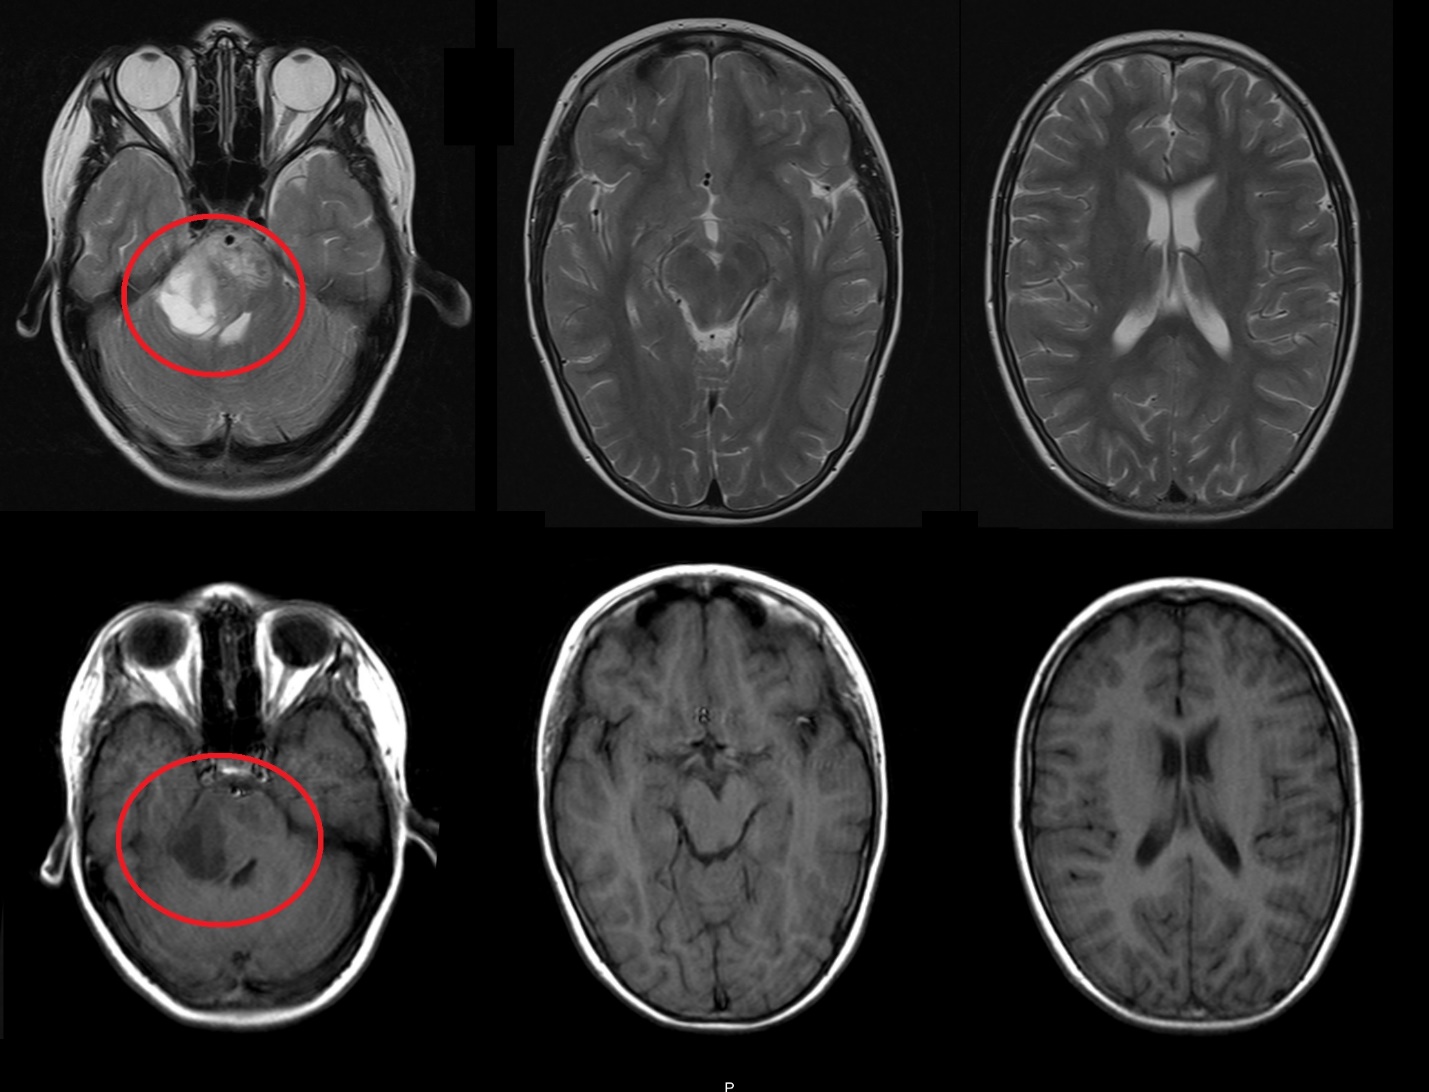

Результаты. У 19 пациентов (50 % от 38 прошедших биопсию) по данным иммуногистохимического анализа послеоперационного материала была выявлена мутация К27М в гене H3F3A. У 6 (15 %) пациентов из 38 МРТ в сроки от 2 до 5 мес (медиана – 4,5 мес) после окончания лучевой терапии выявлено нехарактерное прогрессирование ДСГ в виде метастазирования по желудочковой системе головного мозга. У остальных пациентов когорты исследования, не проходивших процедуру биопсии, подобный характер прогрессирования не наблюдался (p<0,002): у них, как правило, отмечался продолженный рост опухоли (n=96), у 4 больных диагностировано лептоменингеальное метастазирование по спинному мозгу.

Заключение. Нами выявлены случаи нетипичного прогрессирования ДСГ в виде метастазирования по желудочковой системе у детей после открытой биопсии опухоли. Есть основания полагать, что биопсия могла способствовать диссеминации ДСГ по ликворным пространствам. Необходим поиск альтернативных методов оценки молекулярно-генетических характеристик ДСГ.